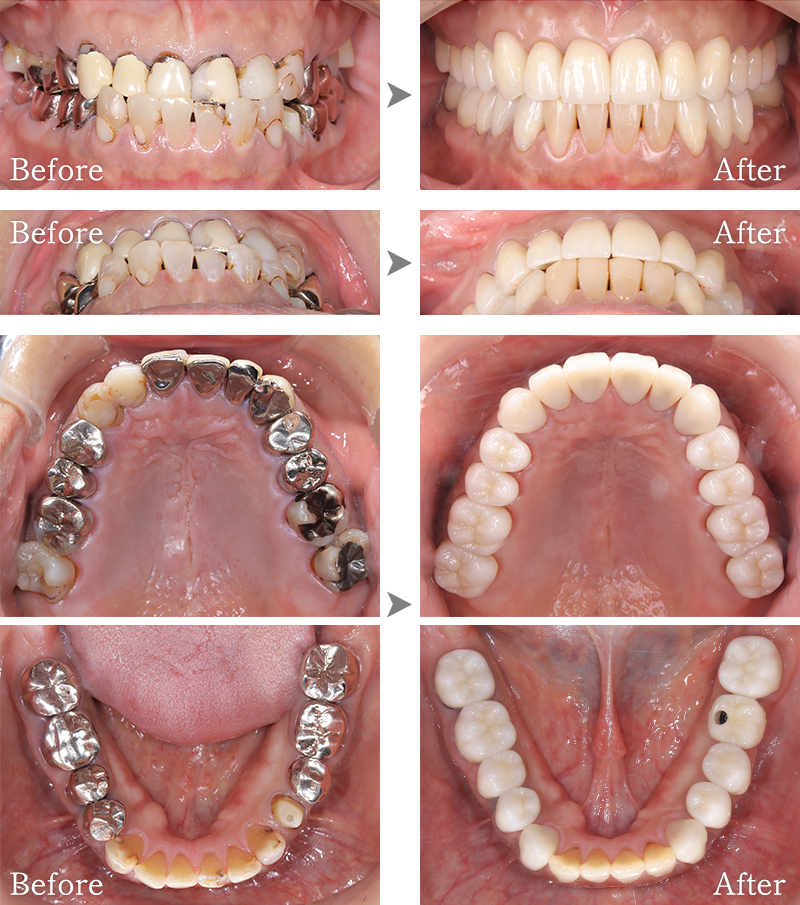

CASE4

骨格1級患者に対し、臼歯部にインプラント治療を行い咬合回復を行なった1症例

マークをスライドしてご覧ください

インプラント症例5

主訴 右側でうまく噛めない

治療内容 下顎臼歯部インプラント、咬合再構成、上顎矯正治療、セラミック治療

治療期間 約2年

費用 診断料:22万円(税込)

下顎顎臼歯部インプラント埋入手術:22万円(税込)×4本

セラミック補綴:22万円(税込)×4本

セラミック治療:11万円(税込)×9本

矯正治療:44万円(税込)